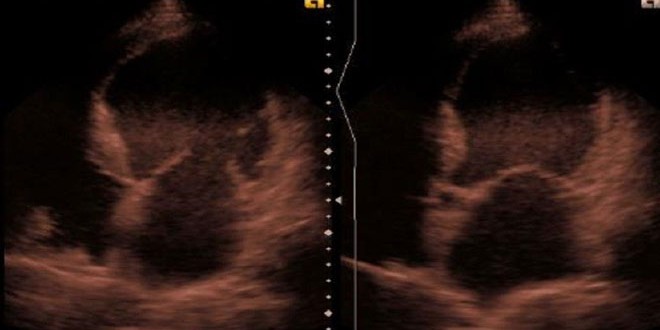

درس فريق من علماء جامعة موسكو الحكومية الآليات الجينية وراء تصلب الأوعية الدموية، واكتشفوا الجين المسؤول عن تطور الجلطة القلبية.

واكتشف الباحثون أن التغيرات في كميات الإنزيم هي ذات أسباب جينية ترتبط بطبيعة بداية مرض النقص في التروية الدموية أي بما قد يتسبب بالجلطة القلبية أو بالارتفاع الثابت في ضغط الدم في أثناء تطبيق جهد ما، وهو ما يدل على أن ذلك الإنزيم يشارك في تطور التصلب في الأوعية ويمكنه أن يؤثر على مدى ثبات واستمرار تصلب الأوعية.